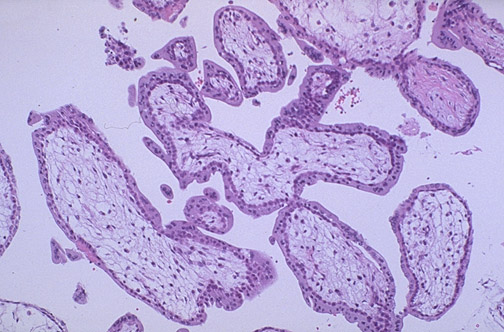

| In the first trimester, the chorionic villi of the placenta are large and covered by two layers of cells--the darker inner cytotrophoblast and the outer syncytiotrophoblast with abundant pink cytoplasm. The blood vessels within each villus are not prominent at this time. Maternal blood circulates between the villi |